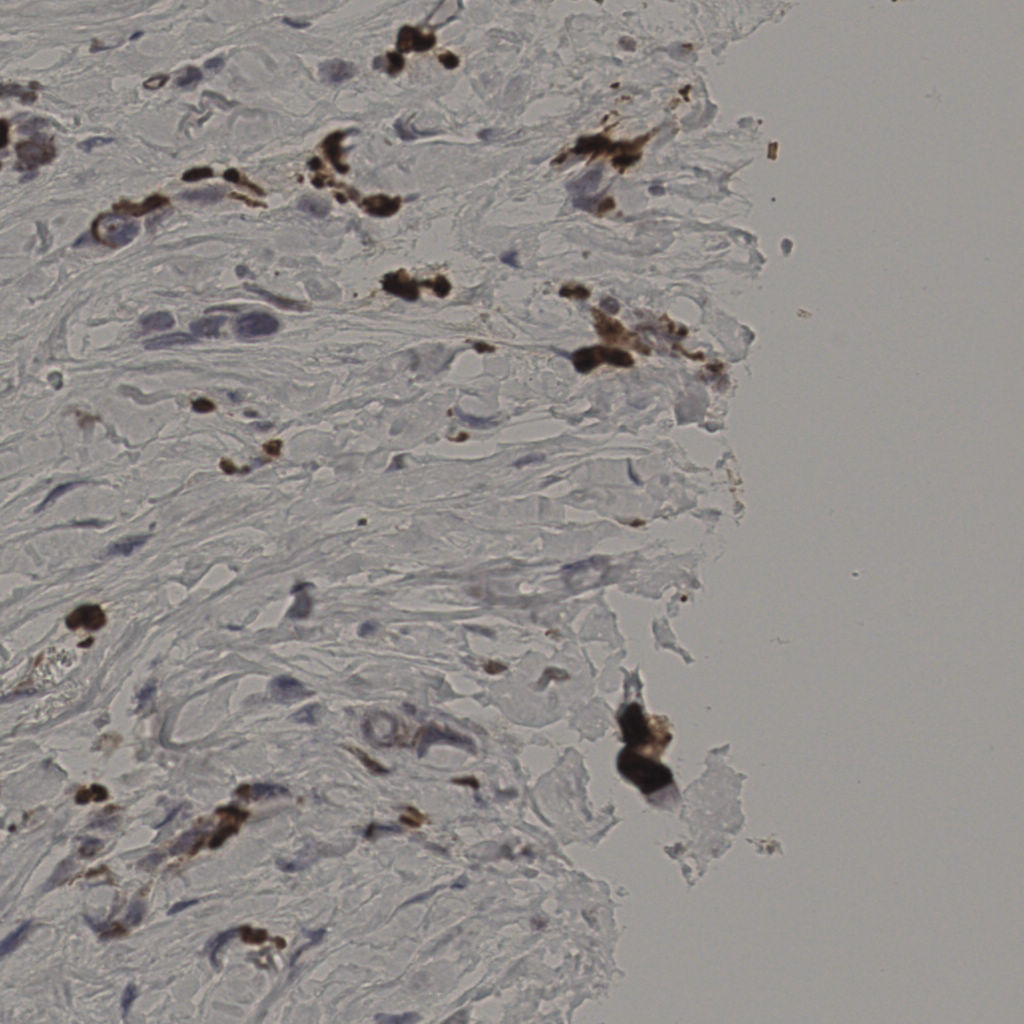

17.75%

Ki67 指数

阴 7986

阳 1723

slice_22_9_x19712...

slice_23_13_x2060...

slice_23_14_x2060...

slice_23_15_x2060...

slice_23_16_x2060...

slice_23_17_x2060...

slice_23_18_x2060...

slice_23_19_x2060...

slice_23_36_x2060...

slice_23_37_x2060...

slice_23_38_x2060...

slice_23_39_x2060...

slice_23_40_x2060...

slice_23_41_x2060...

slice_23_42_x2060...

slice_23_46_x2060...

slice_24_13_x2150...

slice_24_14_x2150...

slice_24_15_x2150...

slice_24_16_x2150...